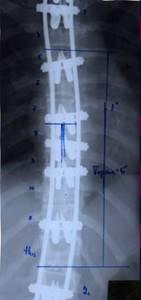

| Различные варианты однопластинчатого эндокорректора |

| Двухпластинчатый эндокорректор с многоуровневой фиксацией |

| Больная Л-ч, 12 лет сколиоз IV степени |

Результат оперативного лечения |